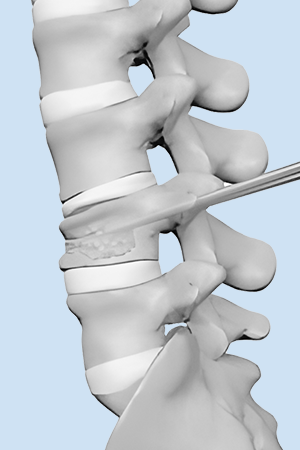

בלון kyphoplasty הוא הליך זעיר פולשני שנועד לתקן שברי דחיסה בחוליות על ידי צמצום וייצוב השבר. הוא מטפל בשברים פתולוגיים של גוף החוליה עקב אוסטאופורוזיס, סרטן או נגעים שפירים.

טיפול סימפטומטי קונבנציונלי כולל משככי כאבים בפה, הקרנות פליאטיביות, ניתוחים וטיפול סיסטמי כגון ביספוספונטים. מטופלים רבים נאבקים בטיפולים אלו עקב ביקורים חוזרים, יעילות ירודה ותופעות לוואי. בשנת 1984, המנתח הצרפתי Galibert דיווח על יישום הזרקת מלט עצם דרך עורית בטיפול בכאב בלתי פתיר הנגרם על ידי המנגיומה השנייה של עמוד השדרה הצווארי, ויצר תקדים להזרקת מלט עצם עורית זעיר פולשנית בטיפול בנגעים בחוליות. תוך 48 שעות לאחר ניתוח ורטרופלסטיה מלעורית (PVP) או קיפופלסטיקה בלון מלעורית (PKP), הקלה משמעותית בכאב הייתה קשורה להפחתת השימוש בתרופות ולשיפור הפרמטרים התפקודיים.